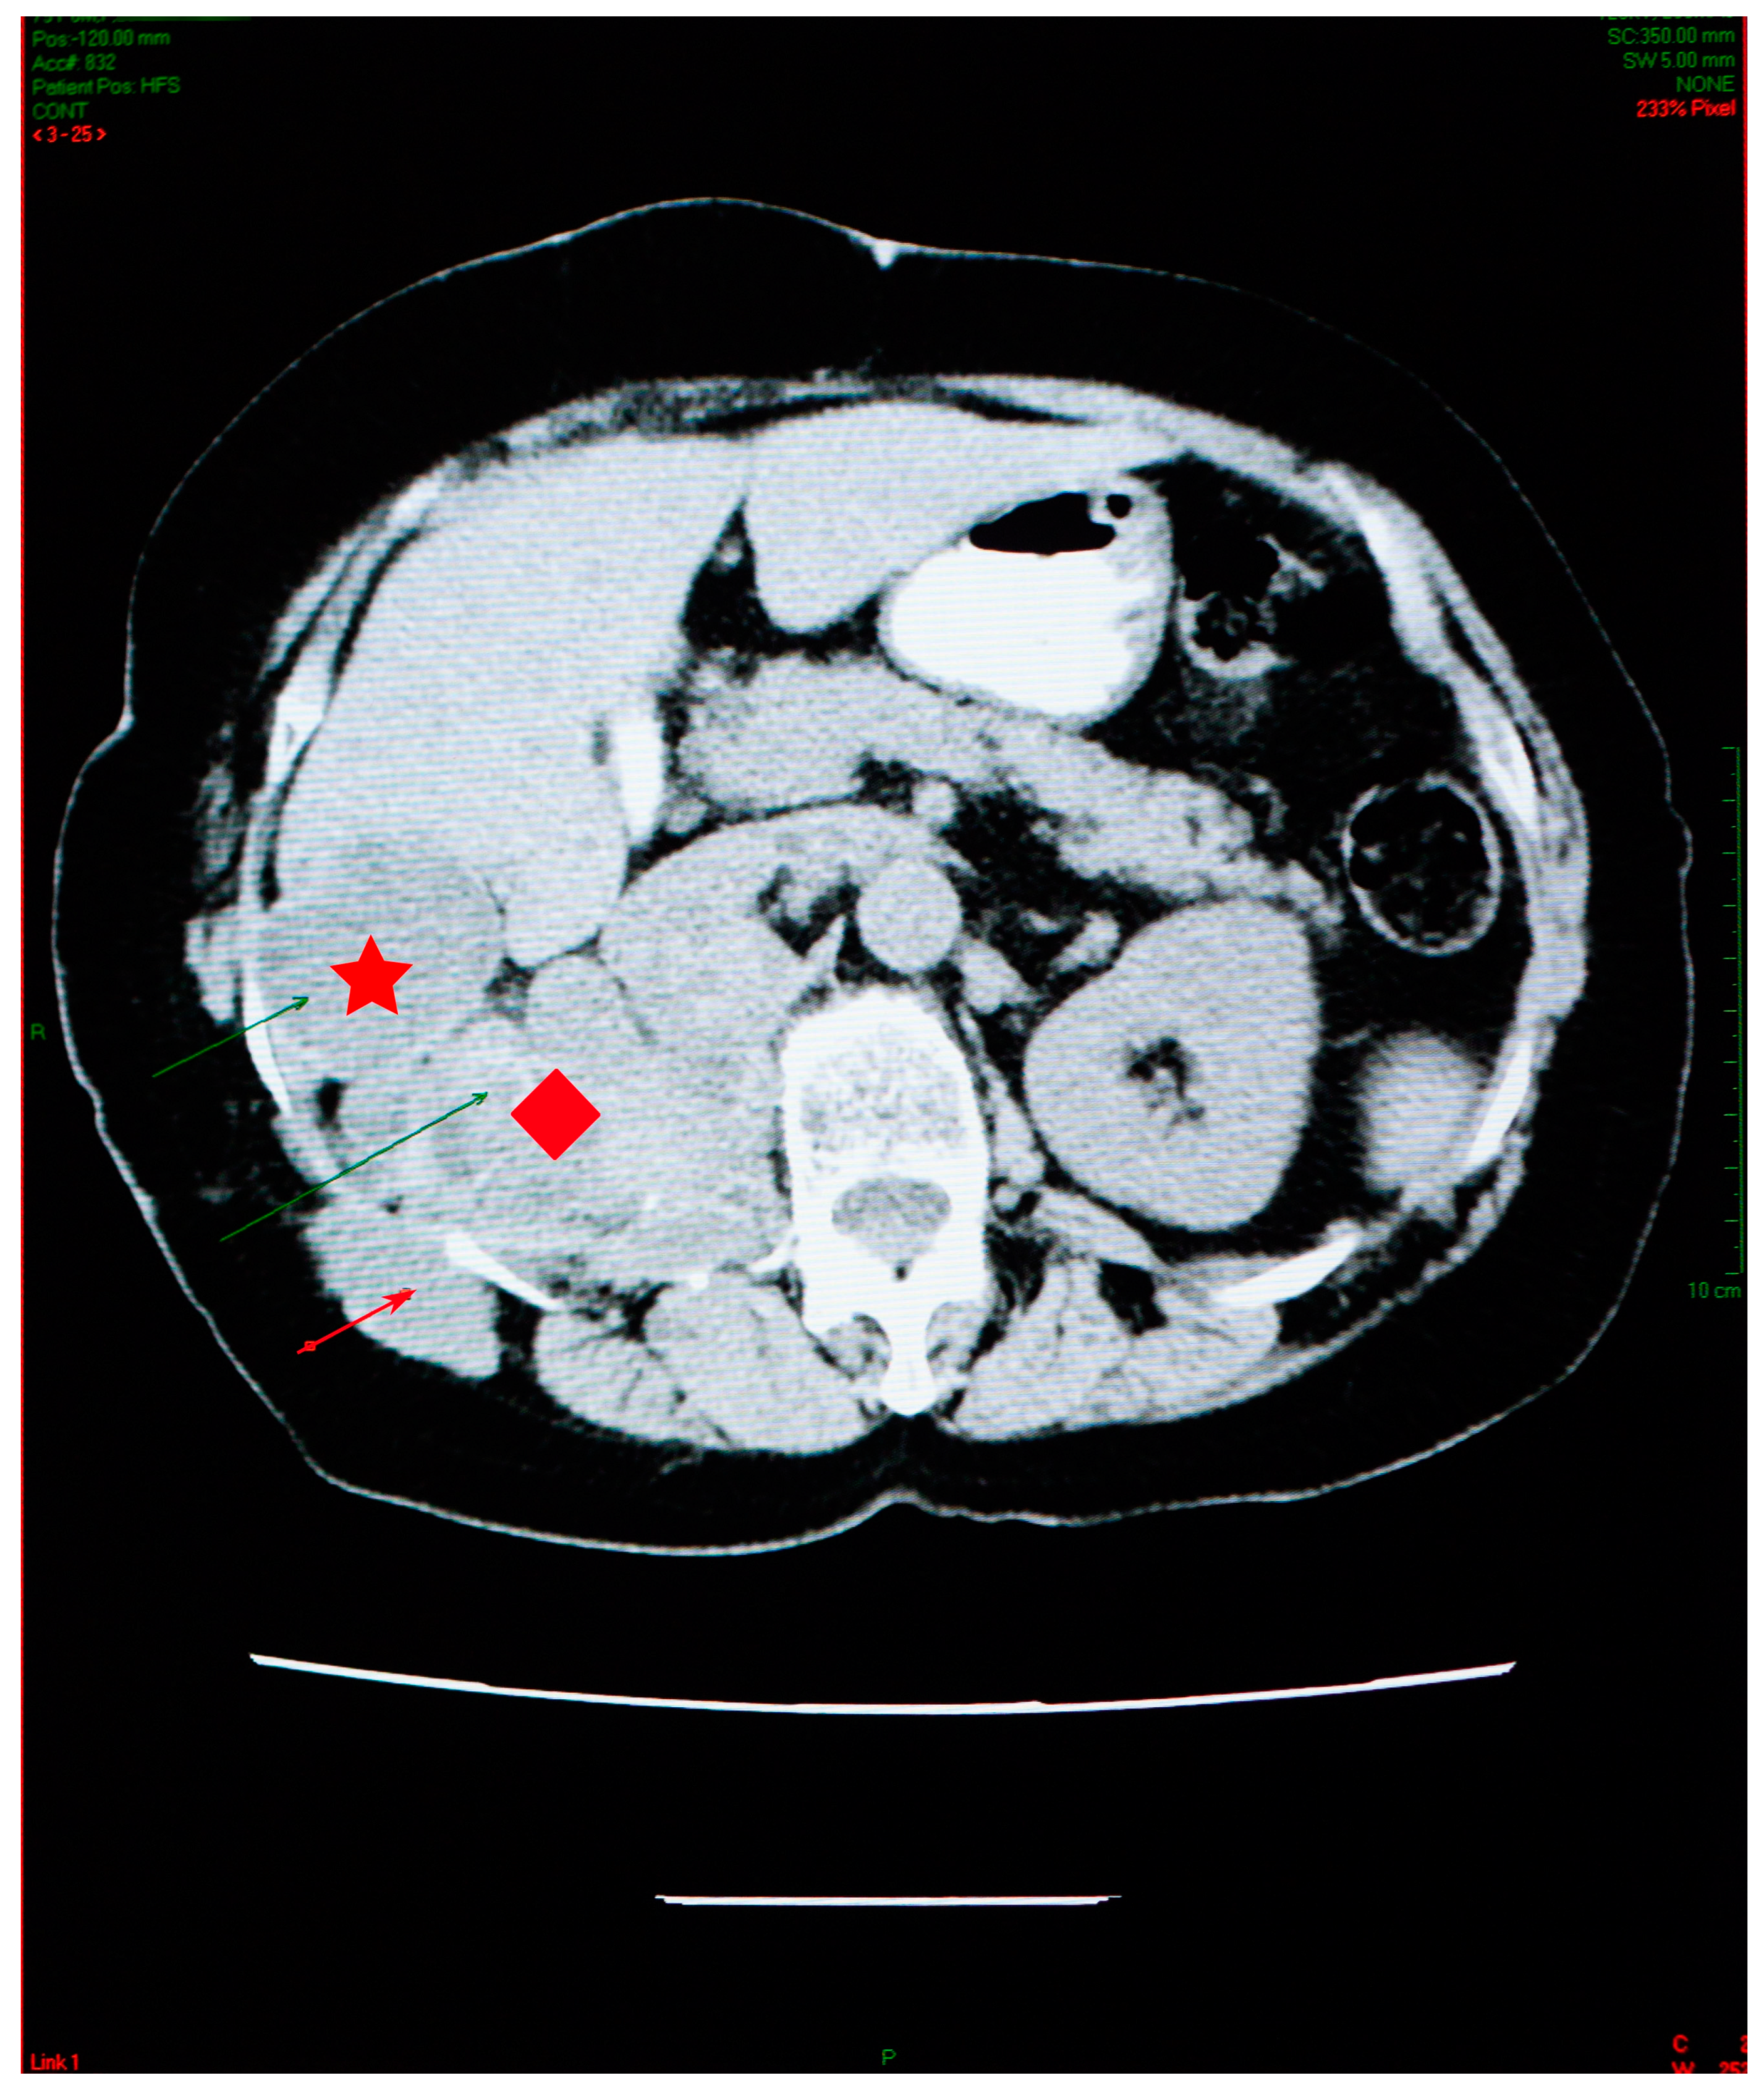

At her check-up in October 2006, the thoracic radiograph raised the suspicion of lung metastases from a cancer of unknown location (numerous 1–2 cm opacities, with bilateral lung dissemination) (Figure 1).

Abdominal imaging revealed multiple cysts, with lots of septa, confluent in the right kidney space, invading the retroperitoneal area down into the right pelvic region, situated between the aorta and the vena cava. Similar types of damage were visible in the sixth right liver segment, as well as the right iliac fossa, and the right paravertebral region (Figure 3).

The right kidney could not be visualized. The psoas muscle, along with the spaces between intestinal loops, had been infiltrated by the same sort of septate cystic masses. A somewhat larger mass, with a size of 45/33 mm, was observed adjacent to the bowel on the right side. The specific serology was intensely positive.

Figure 3. Abdominal CT scan showing multiple cysts, confluent in the right kidney space (red diamond), invading the retroperitoneal area, in the sixth right liver segment (star) and in the right iliac fossa and right paravertebral area (arrow).